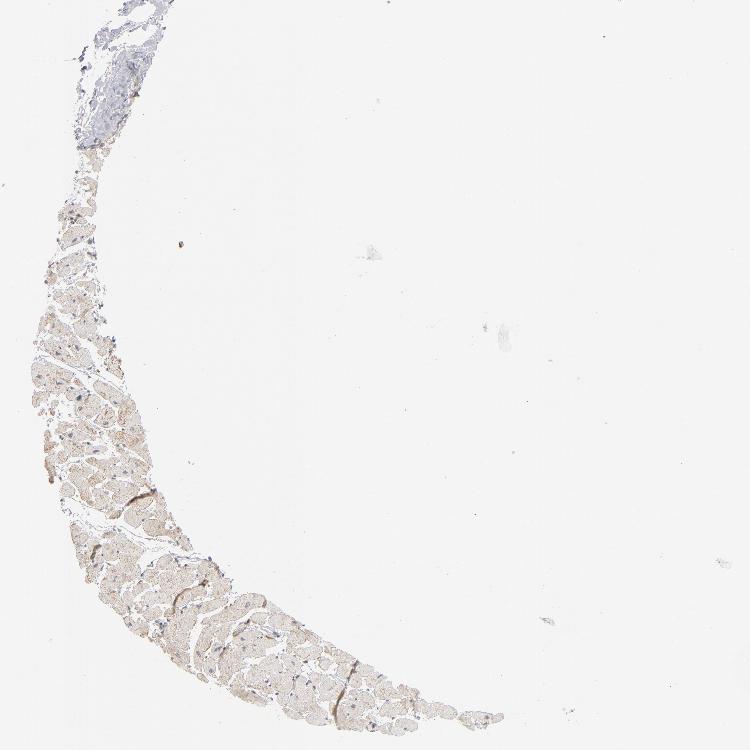

HEART MUSCLE - Antibody stainingi

Antibody staining in the annotated cell types in the current human tissue is reported as not detected, low, medium, or high, based on conventional immunohistochemistry profiling in selected tissues. This score is based on the combination of the staining intensity and fraction of stained cells.

Each image is clickable and will lead to virtual microscopy that enables deeper exploration of all samples and also displays staining intensity scores, fraction scores and subcellular localization as well as patient and tissue information for each sample.

Antibody HPA002033

Cardiomyocytes Not detected